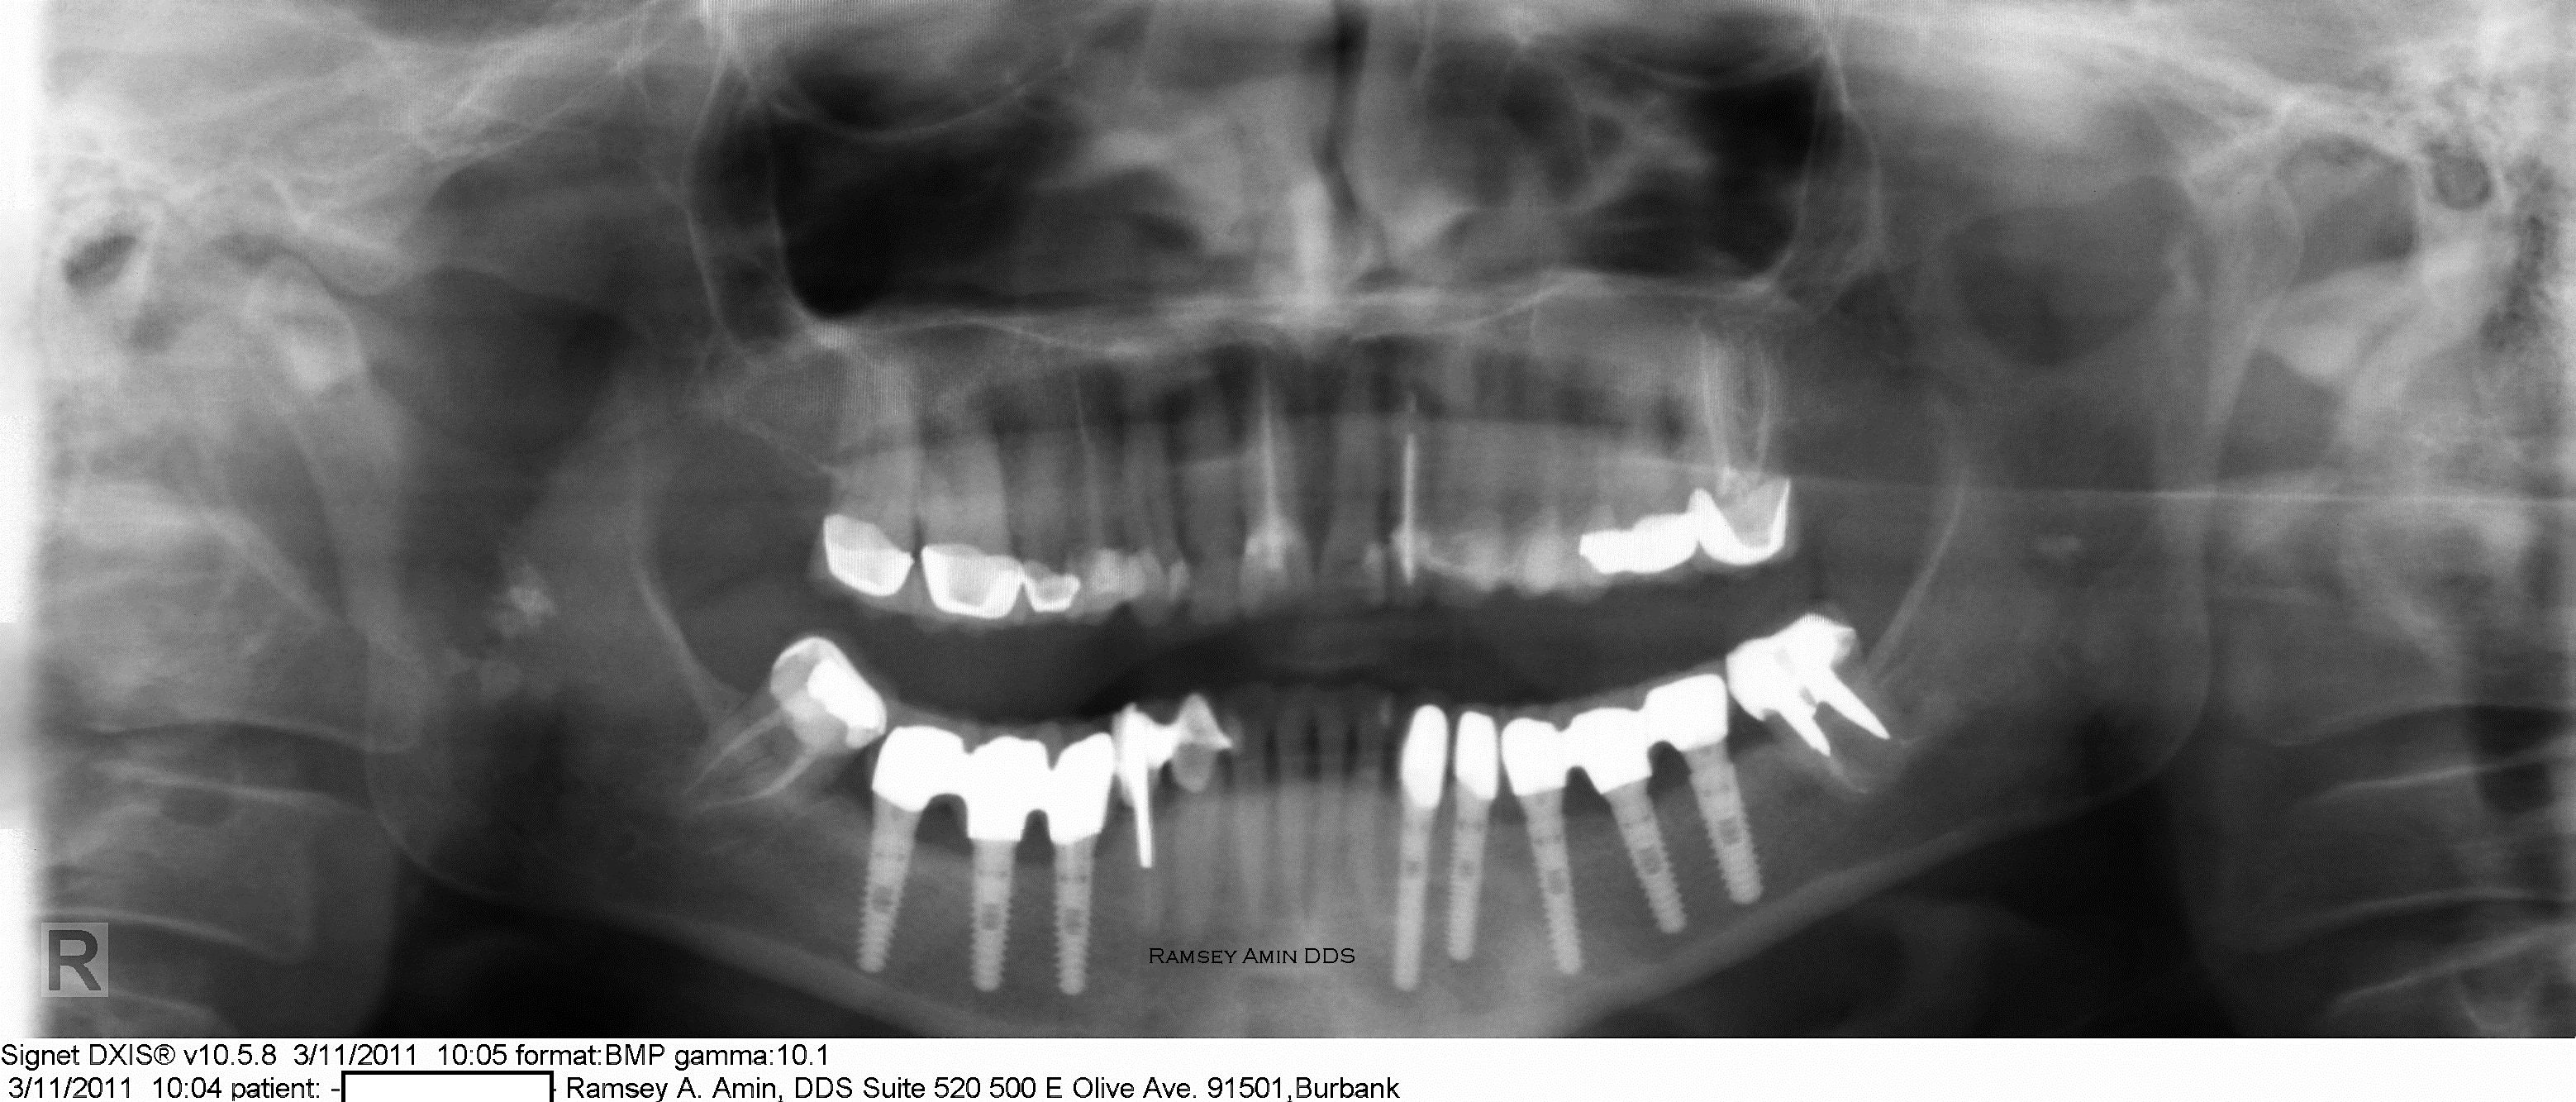

From www.burbankdentalimplants.com

Nerve Reposition Lower Dental Implants Ramsey Amin DDS Ramsey What Is Dental Nerve Treatment The center of your tooth, known as the pulp, houses nerves, blood vessels, and connective tissues. Here’s what you need to know to help stop the. Can home remedies permanently cure tooth nerve pain? Root canal is a dental procedure to repair and save your tooth when it's badly decayed, damaged,. Learn about the causes, symptoms, preventive measures, and effective. What Is Dental Nerve Treatment.